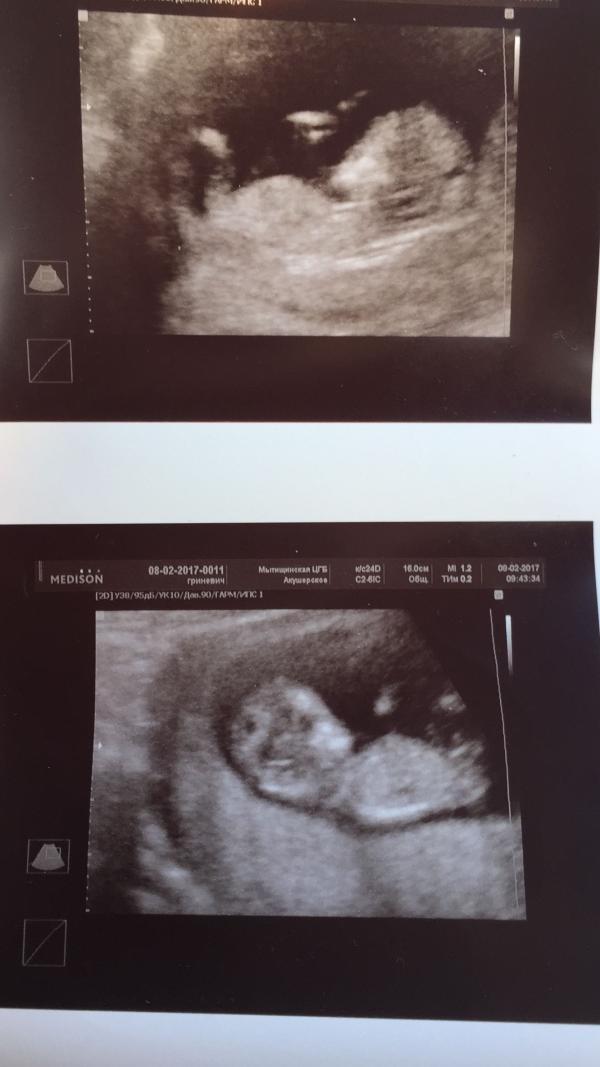

задержка, тесты сначала показывали одну полоску, день на 9-10 начала появляться еле заметная вторая полоска, которую видела только я 🤦🏼♀️😂 30-го декабря пошла в ЖК, врач подтвердил беременность 🤰🏼 ,срок по матке поставил меньше на неделю, на УЗИ не ходила! В середине января пошла вставать на учёт (срок так же ставили меньше на неделю) Токсикоз был не очень сильный 🤗 Записалась на скрининг. Сегодня его благополучно прошли. В общем у нас будут БЛИЗНЕЦЫ 😍🙈 Мы в шоке🙈🙈🙈